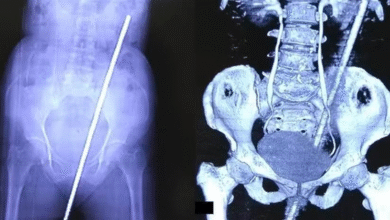

Homem de 60 anos vai parar em hospital por motivo inusitado, objeto de um metro entrou dentro do ân… Ver mais

Na última terça-feira (14/1), um caso atípico chamou a atenção no Hospital de Emergência e Trauma Senador Humberto Lucena, em…